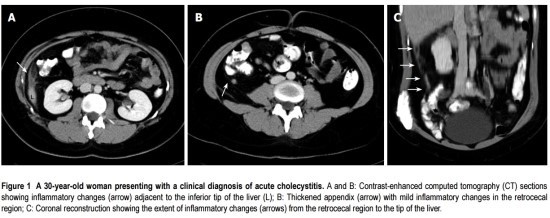

다음의 두 CT를 보면 충수돌기는 대장의 뒤쪽에 위치하며 염증성 변화가 간까지 올라가 있는 것을 볼 수 있다.

참조> World J Gastroenterol 2009 July 28; 15(28): 3576-3579